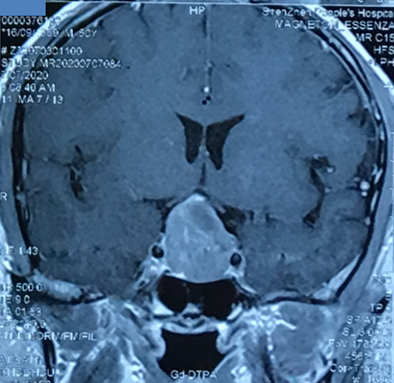

肿瘤切除后,需要复查,了解是否有肿瘤残留、复发,判断复发肿瘤与周围血管、神经的关系。对于库欣病术前微小肿瘤的辨认、可疑复发的识别、特殊病例的影像解读,异常重要。

巨大垂体瘤,术前患者视力、视野情况,视神经损伤程度情况、术后改善情况,均需要眼科医生提供帮助。